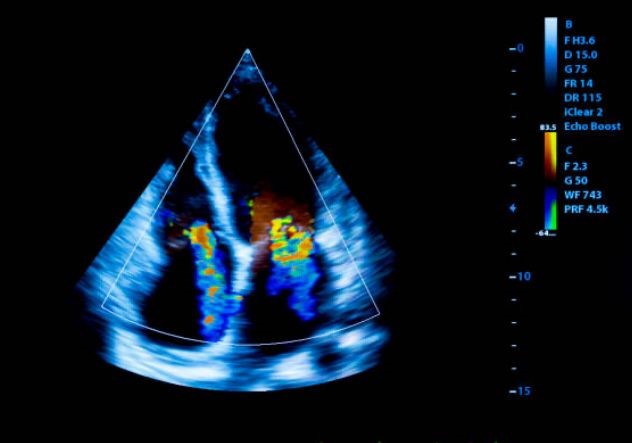

Ecocardiograma Doppler Color

Utiliza ultrasonido para visualizar el corazón en tiempo real, evaluando su estructura y el flujo sanguíneo sin ningún dolor.

Ecocadiograma Ecocardiograma

Ecocardiograma

Un ecocardiograma Doppler es una prueba no invasiva que utiliza ultrasonido para evaluar la estructura y función del corazón, medir la velocidad y dirección del flujo sanguíneo, lo que ayuda a diagnosticar diversas enfermedades cardíacas.

¿Para qué se utiliza?

• Diagnóstico de enfermedades cardíacas como insuficiencia cardíaca, problemas de válvulas, miocardiopatías, cardiopatías congénitas, entre otras.

• Evaluación del flujo sanguíneo y la función de las válvulas.

• Monitoreo de la evolución de enfermedades cardíacas.

Preparación y Duración

Generalmente, no requiere preparación especial. En algunos casos, el médico puede recomendar ayuno o evitar ciertos medicamentos antes de la prueba. La prueba suele durar entre 20 y 30 minutos.

Beneficios:

• No es invasivo, no causa dolor ni requiere radiación.

• Ayuda a diagnosticar y monitorizar enfermedades cardíacas.

• Es una herramienta fundamental para la evaluación cardiovascular.